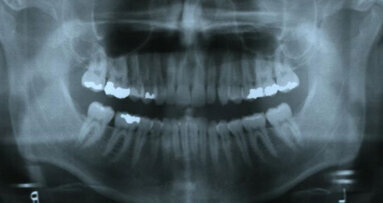

Relapse of mandibular anterior crowding occurs in many well-treated cases, whether they had bicuspid extraction, non-extraction treatment, third molar removal, non-removal or agenesis. Why? Is it related to (a) form and function, (b) tooth-mass issues, (c) occlusion, (d) temporomandibular relationship, (e) arch length discrepancy, (f) heredity, (g) orofacial musculature, (h) intra-oral forces, (i) extraoral forces or (j) oral habits?

For many years, the implication has been that nonextraction orthodontic cases might result in a higher percentage of postretention lower anterior crowding compared to extraction cases, but do they? Review of the literature regarding the effects that third molars have on lower anterior crowding presents both agreement and opposition for both sides of the problem, but the bulk of the evidence seems to indicate that third molars play an insignificant role in lower anterior crowding.